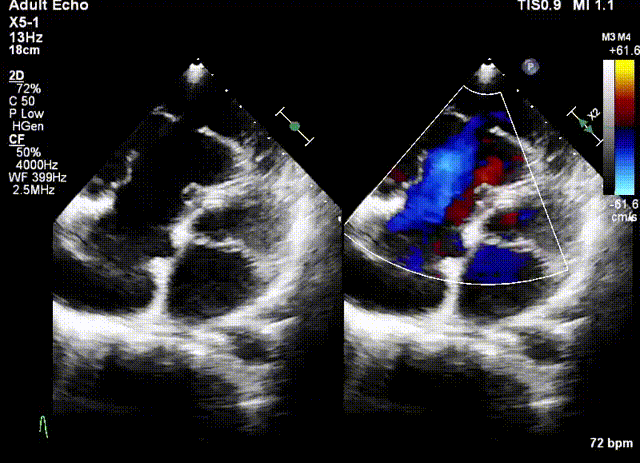

術前超聲

手術在全麻狀態(tài)下開展,此次手術采用經(jīng)頸靜脈入路的方式。在TEE及DSA雙重引導下,術者調(diào)整輸送器頭端角度使得其與三尖瓣瓣環(huán)平面垂直。在輸送器進入右心室后釋放室間隔錨定裝置,而后釋放瓣葉夾持件(2個耳片結構)成垂直狀態(tài)。在TEE及DSA確定夾持件固定至三尖瓣葉根部且位于右室側后釋放人工瓣心房側盤片。隨后調(diào)整瓣膜同軸性以及室間隔錨定件位置(貼合室間隔),進而釋放室間隔錨定裝置,并再次確認瓣膜位置、穩(wěn)定性及同軸性,解離人工瓣膜與輸送器間連接,并撤出輸送器,完成了LuX-Valve Plus人工三尖瓣瓣膜的植入。

陸方林教授通過遠程線上帶教的方式,與林逸賢教授團隊共同完成了此次LuX-Valve Plus人工瓣膜的首例植入。術后食道超聲提示三尖瓣反流完全消失,無瓣周漏,且LuX-Valve Plus人工瓣膜的兩個夾持鍵成功抓取瓣葉,錨定牢固,人工瓣膜穩(wěn)定性良好。